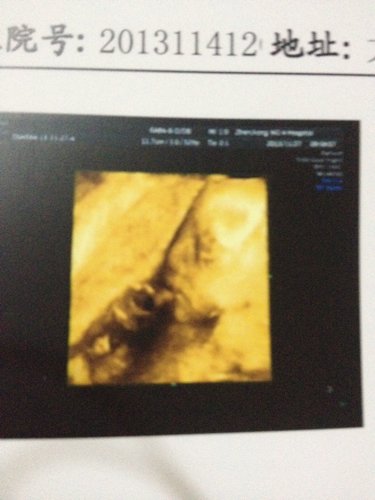

24周四维彩超宝宝的照片如下,当时医生说一切正常。就没多想也没多问,回家后发现没看到宝宝耳朵。单子下面也没有提到耳朵,只提到鼻子,嘴和眼睛。正常吗?

应该是没事的,耳朵可能是宝宝转身的时候挡起来了!不要担心!

四维彩超是检查不出听力的,只能从外观上的特征来判断孩子的健康状况。听力应该没有问题的,放心好了!!祝您宝宝健康成长。